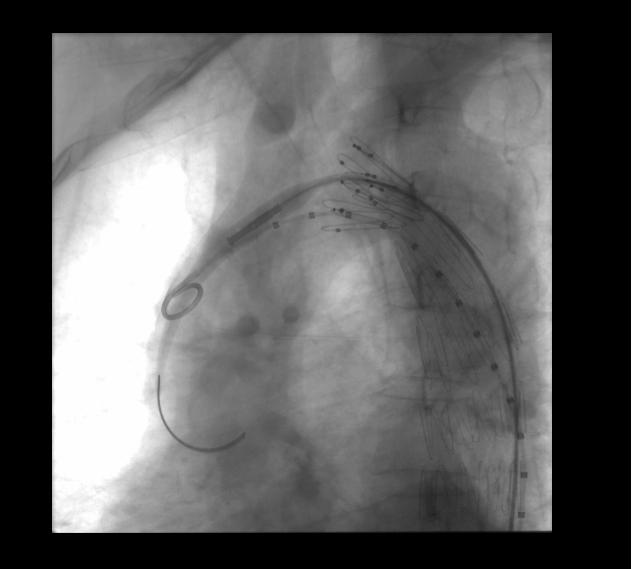

EVAR